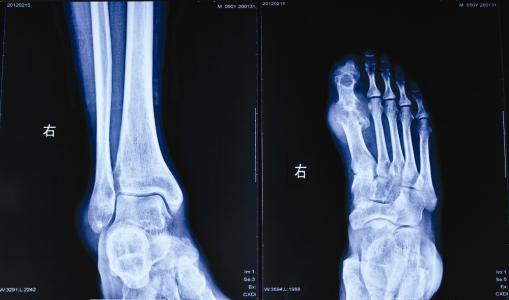

急性痛风性关节炎,是由于尿酸盐结晶脱落所引起的炎症反应。典型发作者,起病急剧,多在午夜足痛惊醒,疼痛高峰在48小时左右,状如刀割和咬噬样剧痛。局部明显红肿热痛。60%~70%患者首次发作在单侧拇趾关节...[详细]

在生活中,我们对于痛风并不陌生,疾病有着剧烈的疼痛,使得患者痛苦不已。 郑州痛风医院 专家表示:如果不注意治疗,疾病还会发展为痛风石,由此造成的危害更加严重。痛风石的病程比较长,严重还会使得患者...[详细]